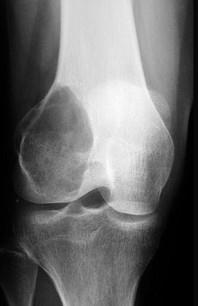

问题 骨巨细胞瘤X线表现如图为 ( )

选项 A、骨端偏心性溶骨性破坏而无骨膜反应 B、骨性破坏,可见片状钙化 C、骨破坏,可见Codman三角 D、位于干骺端,可见有分隔 E、外生性,可见明显破坏

答案 A